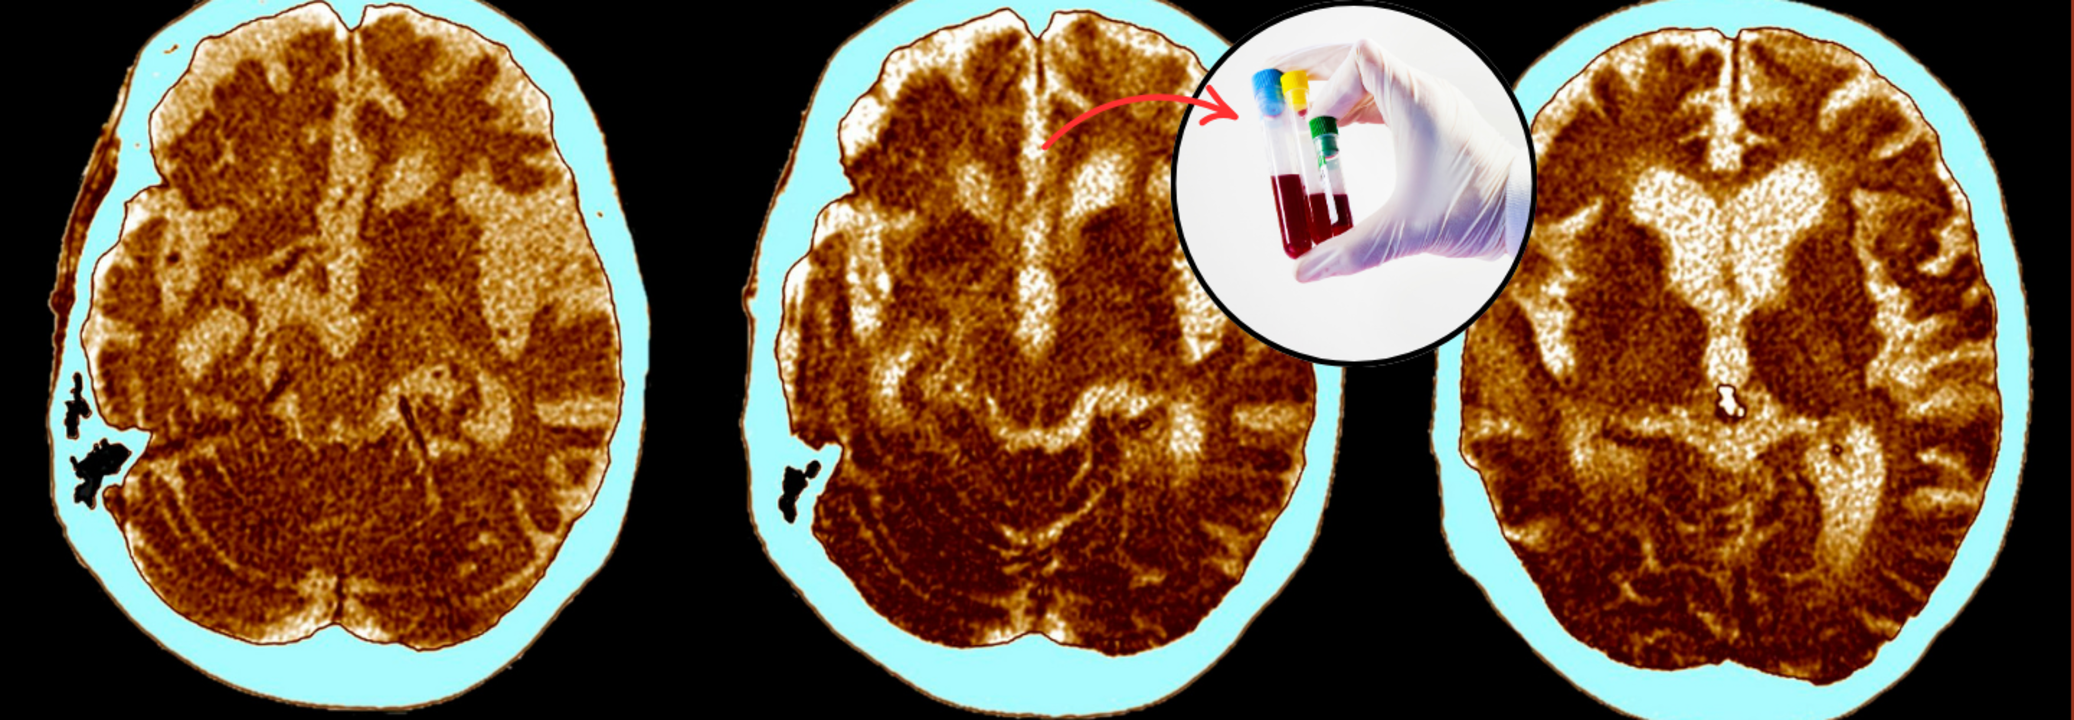

No More Brain Scans Needed, A Simple Blood Test Could Identify Alzheimer’s At Any Stage

SummaryWith nearly 55 million people worldwide currently living with dementia—and Alzheimer’s accounting for 60–70% of those cases—the global burden is enormous. Diagnosis delays often prevent early intervention, compounding the emotional and financial toll on families and healthcare systems alike.